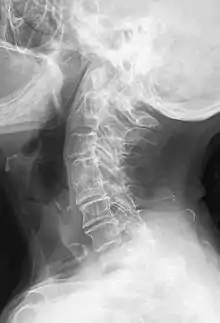

پرتوشناسی یا رادیولوژی (به انگلیسی: Radiology) و گاهی تصویربرداری تشخیصی[1] نام یک رشته از تخصصهای پزشکی است که از پرتو ایکس و دیگر اقسام امواج و پرتوها برای تشخیص و درمان بیماری و حالات غیرطبیعی کمک میگیرد.[2] در تمام اینها، هدف تشخیص بیماری یا حالات غیرطبیعی بدن به کمک روشهای پیشرفته تصویری است. رادیولوژی از کلمه لاتین Radius به معنای پرتو مشتق شدهاست. رادیولوژی دربرگیرنده رشتههای بسیاری است که بر مبنای کاربرد پرتوهای یون ساز برای تشخیص بیماریها یا درمان آنها میباشد.[3]

سابقاً «رادیولوژی» (یا همان پرتوشناسی) اطلاق بر رشتهای میشد که در آن از روشهای پرتوی یونیزان استفاده میشد. اما امروزه «رادیولوژی» با علوم تصویری غیر پرتوی مثل ام آر آی و سونوگرافی نیز خلط میشود.[5] بعبارت دیگر در پرتوشناسی، برخی روشها (همانند سی تی اسکن، ماموگرافی، و روشهای مرسوم رادیوگرافی) از توزیع پرتوهای تابیده شدهٔ اشعه ایکس بر روی صفحات فیلم یا شمارشگرها یا گیرندههای دیگر دیجیتالی تشکیل تصویر میدهند. اما در برخی روشهای دیگر (همانند ام آر آی و سونوگرافی و مقطعنگاری همدوسی اپتیکی) از روشهای غیر پرتوی یونیزان استفاده میگردد. رادیولوژی امروزه هر دو را در بر میگیرد. بعضی اتمها مجموعه ناپایداری از ذرات بنیادی هستند. این اتمها خود به خود اشعه منتشر میکنند و به این ترتیب به اتمهایی با هویت شیمیایی متفاوت تبدیل میشوند. این فرایند که رادیواکتیویته یا پرتوزایی نامیده میشود. توسط هانری بکرل در ۱۸۹۶ کشف شد.[6]

روشهای زیر برای تشخیص مورد استفاده یک رادیولوژیست میتوانند قرار بگیرند: